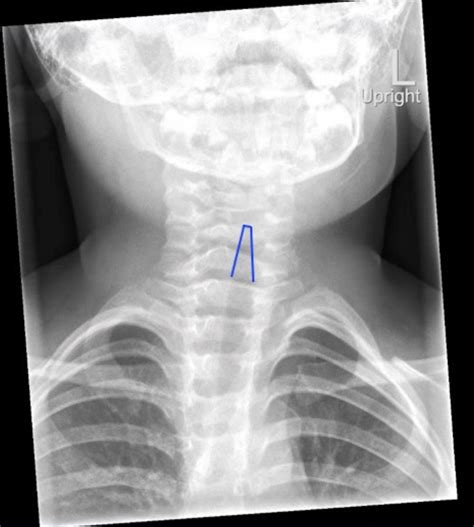

Diagnosing croup typically involves a physical examination by a healthcare provider. The doctor will listen to the child's breathing and assess the symptoms. In some cases, additional tests may be ordered to rule out other conditions, such as:

• Chest X-ray: To check for pneumonia or other lung conditions.